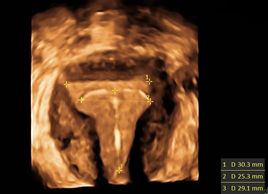

Normal position of an IUD seen on coronal 3D images.

Low and mildly oblique position of an IUD seen on coronal 3D images.